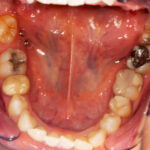

There’s a difference between overall gum puffiness and swollen gums around tooth in one specific area. When it’s limited to a single spot, it tends to stand out more.

Sometimes it’s something simple. Food trapped between teeth, a spot that’s harder to floss, a filling that catches plaque more easily than expected. Other times it’s deeper. A cavity near the gum line can irritate the tissue quietly. Infection near the root can create pressure that shows up as swelling above it.

Localized swelling tends to persist if the source remains. It may look slightly raised compared to the surrounding gum tissue. It may feel tender when chewing. Not every case is severe. But when swelling doesn’t improve within a few days, it usually has a reason.

If swelling is spread out, plaque buildup is often involved. If it’s limited to one area, that tooth may need closer attention. X-rays can show what isn’t visible above the surface.